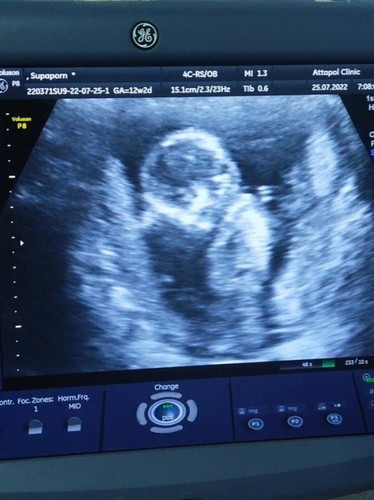

บ้านนี้14w4dแล้ว ยังไม่ทราบเพศลูกเลย ตื่นเต้นมากค่ะ👶🏻💗 #อยากได้ลูกสาว #คนแรกลูกชาย